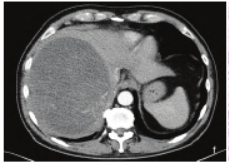

图3 增强CT示动脉晚期于团块内可见迂曲血管影

增强CT提示:寄生虫感染?肿瘤?或其他。患者行“右侧复杂肝占位切除+胆囊切除+门静脉修补+膈肌修补术”,术中见:腹腔内未见积液,脏器间无明显粘连,肝脏大小及形态基本正常,质地稍韧,右肝可见一大小约17 cm×13 cm×10 cm实性占位突出肝脏表面,与膈肌紧密粘连,可疑侵犯膈肌。